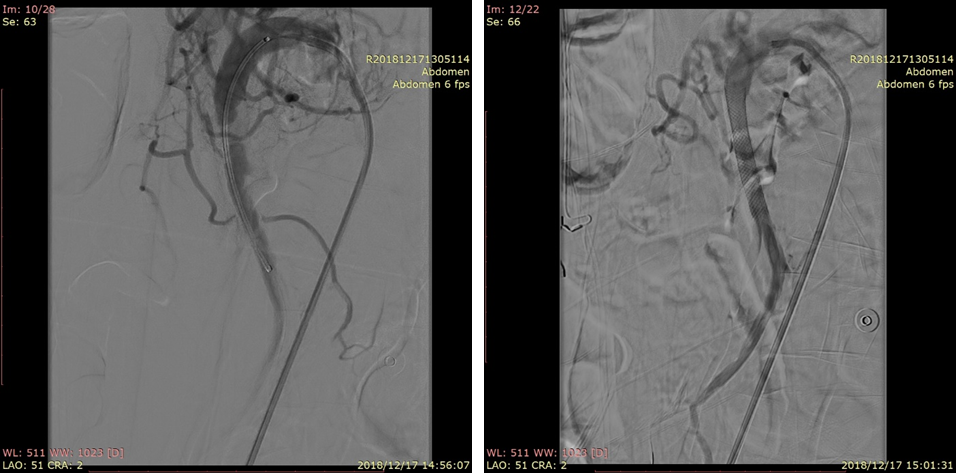

20181217DSA:破口位于距离SMA开口2cm处;破口远端真腔不显影。

20181217DSA:假腔充满血栓

20181217DSA:选择进入远端血管(回肠动脉)

20181217DSA:找到远端真腔血流受限的原因(箭头)

20181217DSA:植入第一枚支架(wallstent7*50mm)

20181217DSA:植入第二枚支架(wallstent9*50mm)

20181217DSA:支架植入后尝试寻找空肠动脉

20181217DSA:支架植入后最终复查造影